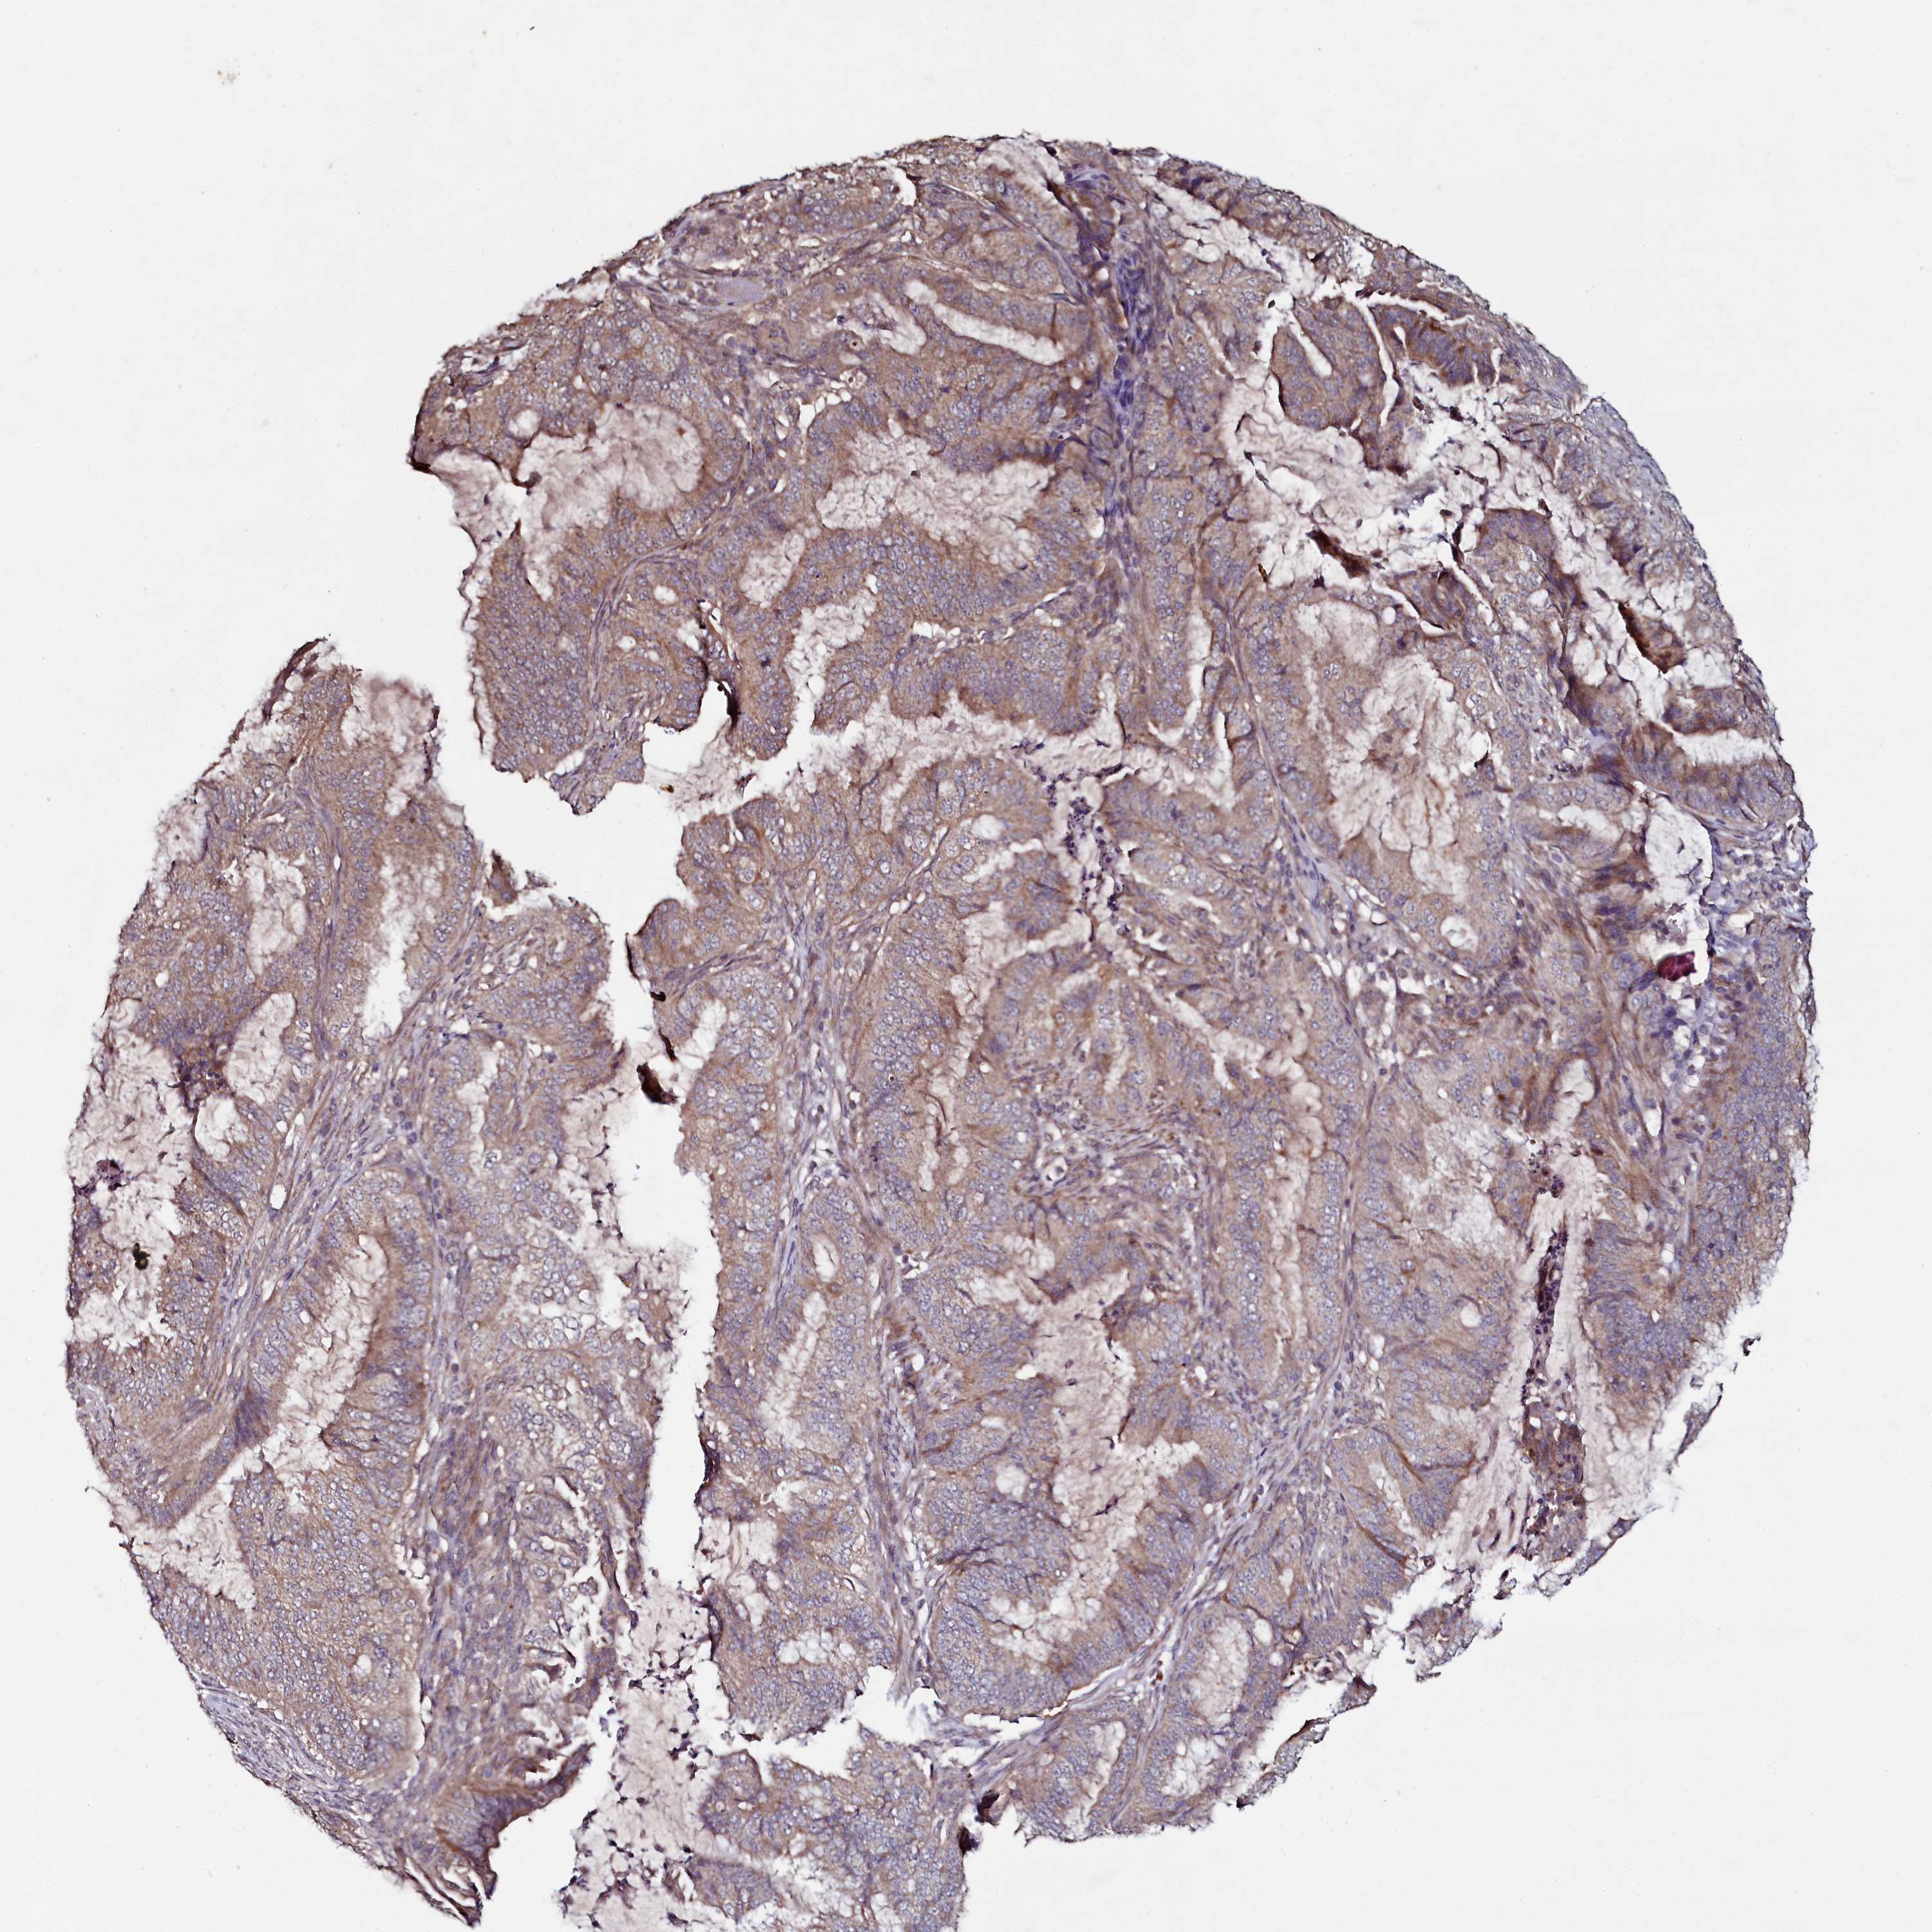

ENDOMETRIAL CANCER - Protein expressioni

A mouse-over function shows sample information and annotation data. Click on an image to view it in a full screen mode. Samples can be filtered based on level of antibody staining by selecting one or several of the following categories: high, medium, low and not detected. The assay and annotation is described here.

Note that samples used for immunohistochemistry by the Human Protein Atlas do not correspond to samples in the TCGA dataset.

Antibody stainingi

Antibody staining in the annotated cell types in the current human tissue is reported as not detected, low, medium, or high, based on conventional immunohistochemistry profiling in selected tissues. This score is based on the combination of the staining intensity and fraction of stained cells.

Each image is clickable and will lead to virtual microscopy that enables deeper exploration of all samples and also displays staining intensity scores, fraction scores and subcellular localization as well as patient and tissue information for each sample.

Antibody HPA040196

Antibody HPA040213

Staining

High

Medium

Low

Not detected

Intensity

Strong

Moderate

Weak

Negative

Quantity

>75%

75%-25%

<25%

None

Location

Nuclear

Cytoplasmic/membranous

Cytoplasmic/membranous,nuclear

Adenocarcinoma, NOS

Adenocarcinoma, metastatic, NOS